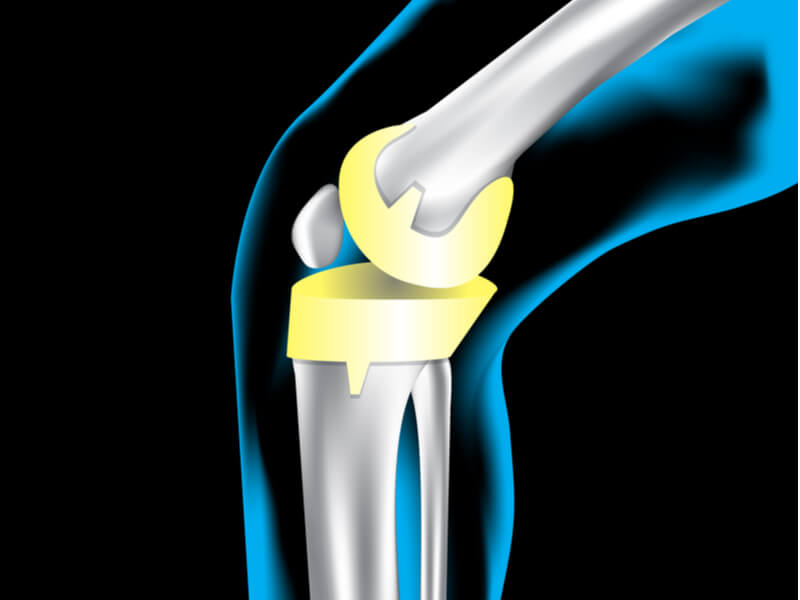

手術中、外科医は損傷した軟骨と骨を除去した後、金属、プラスチック、その他の合成材料で構成される人工関節を移植します。